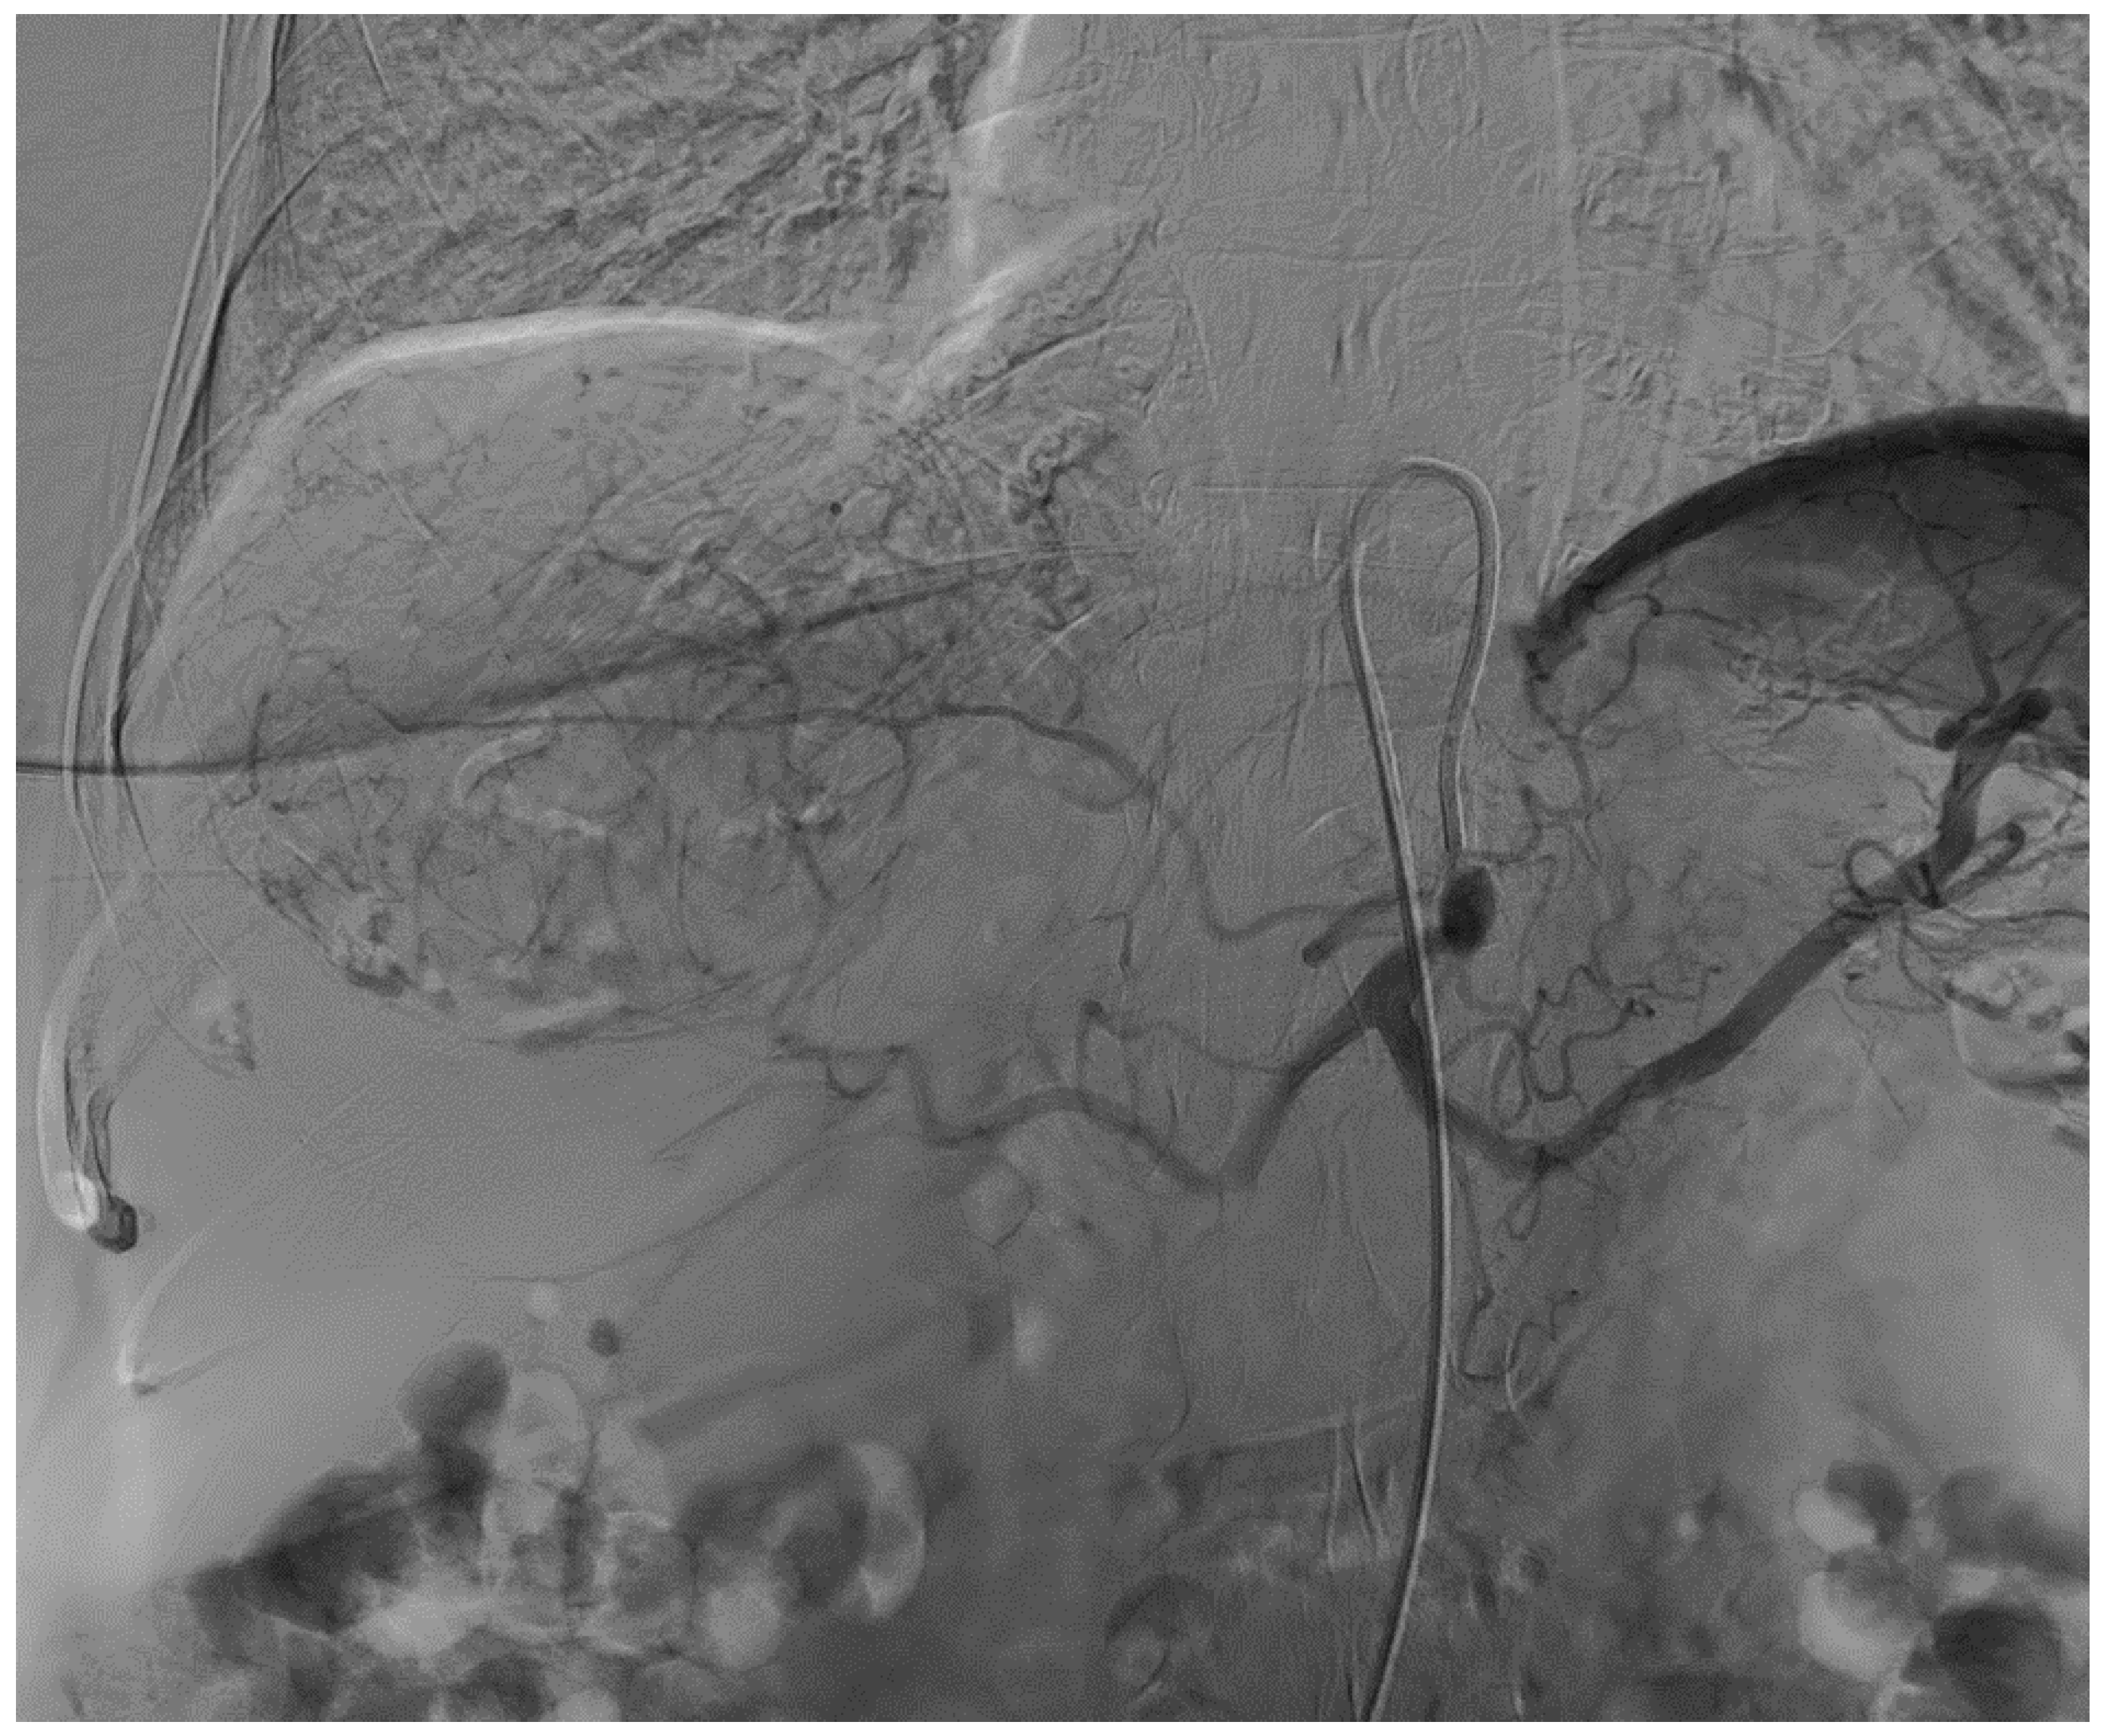

2. Case Report